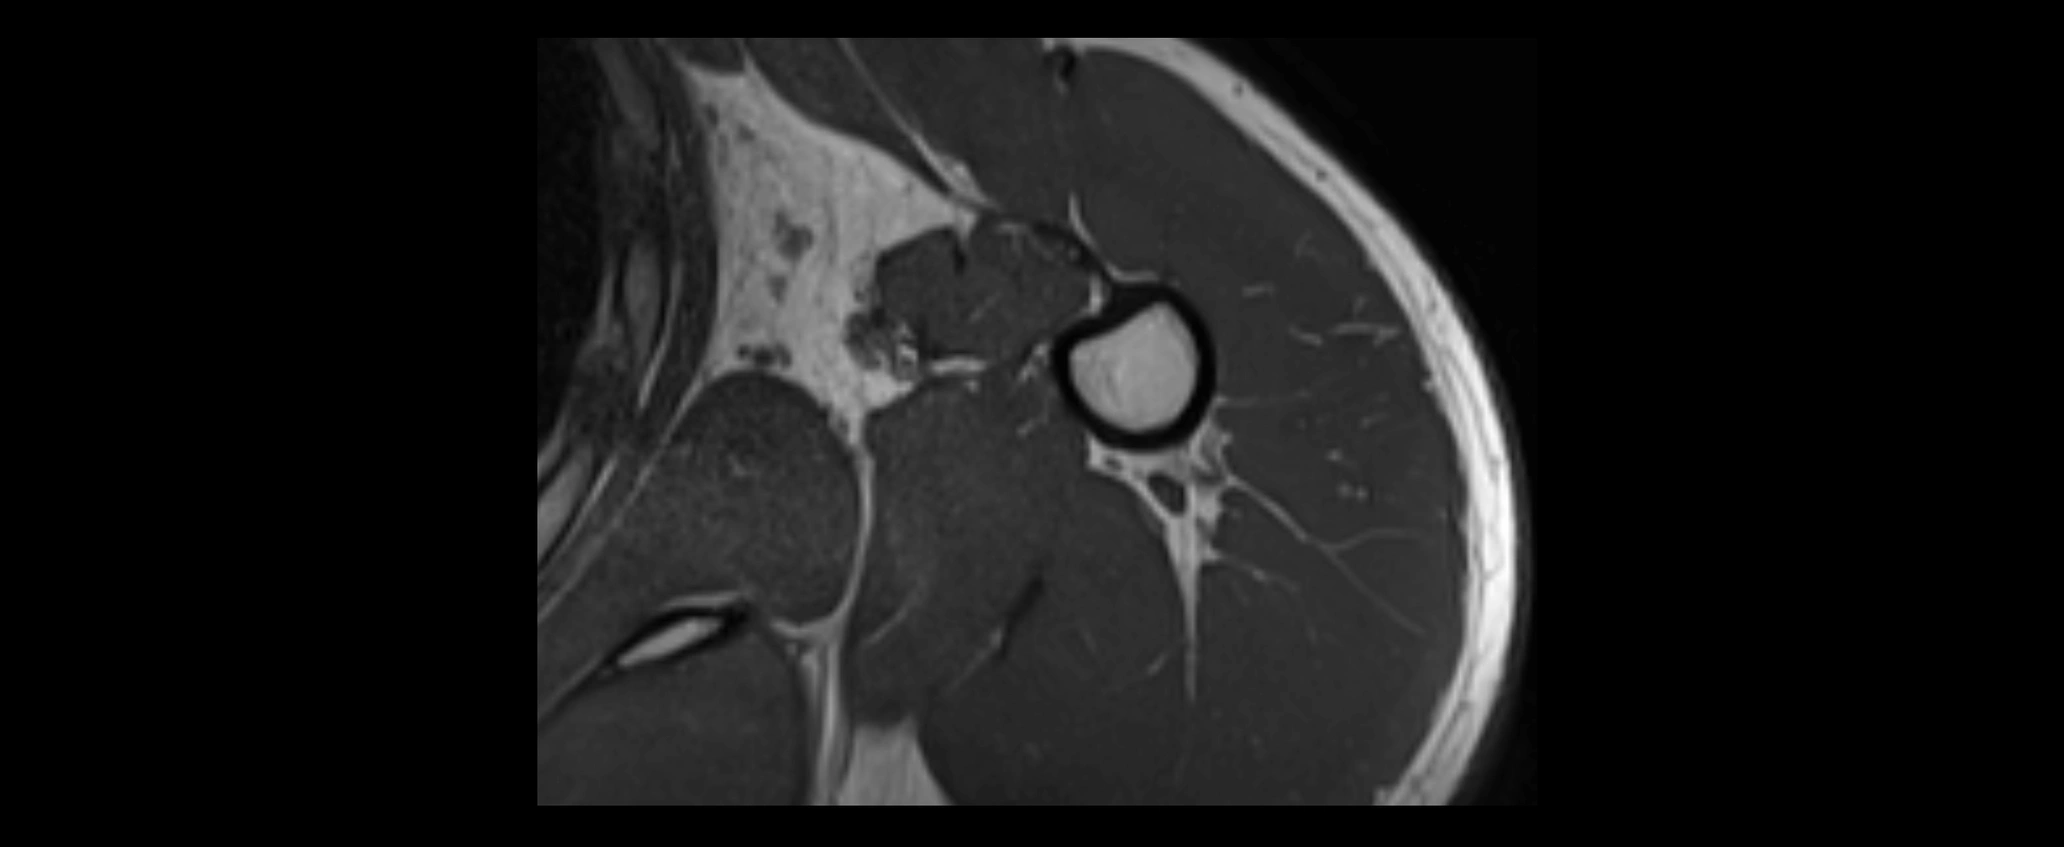

MRI images

image